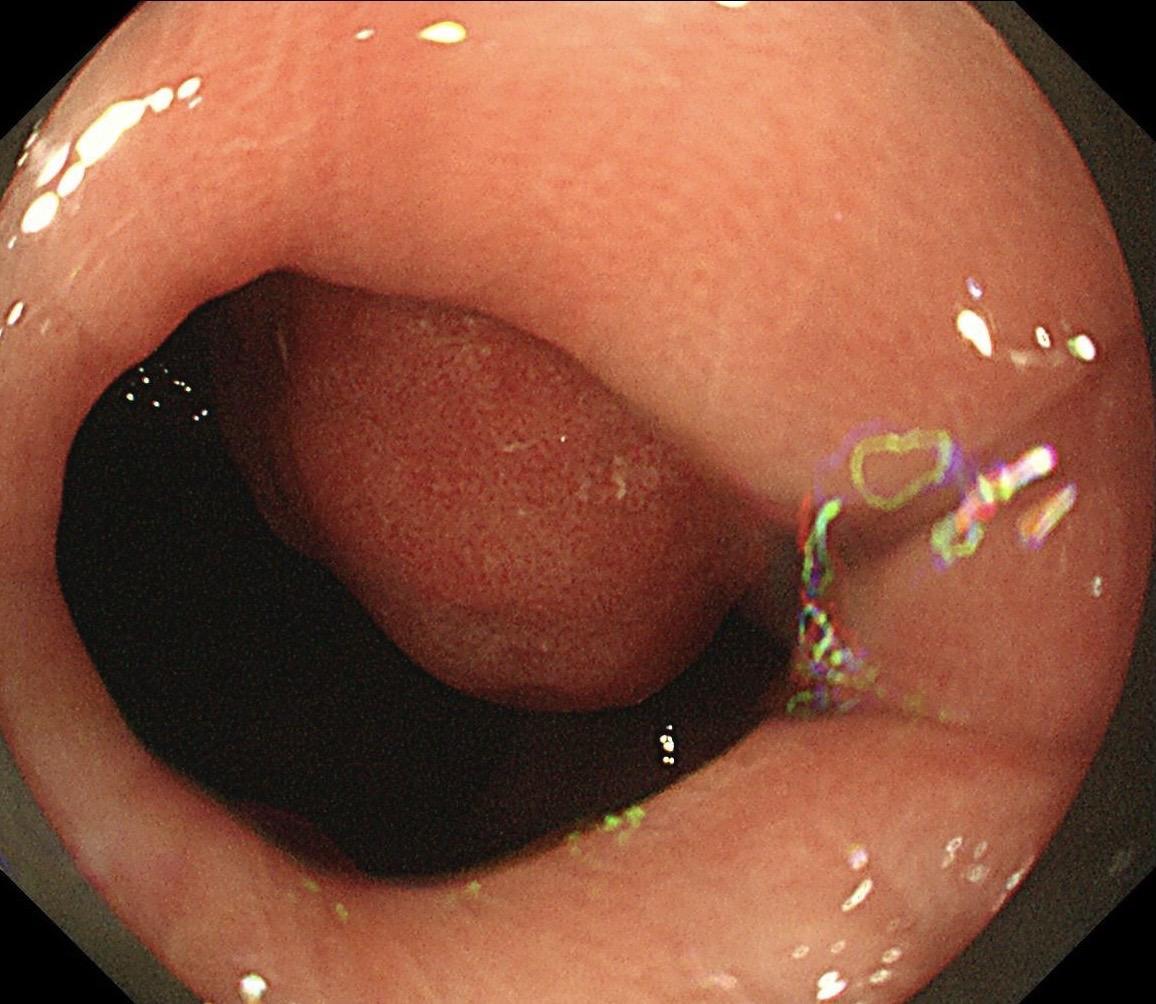

低位早期直肠Ca.男,37岁,大便带血1月,距齿状线2cm,ESD切除,还好来得及时~